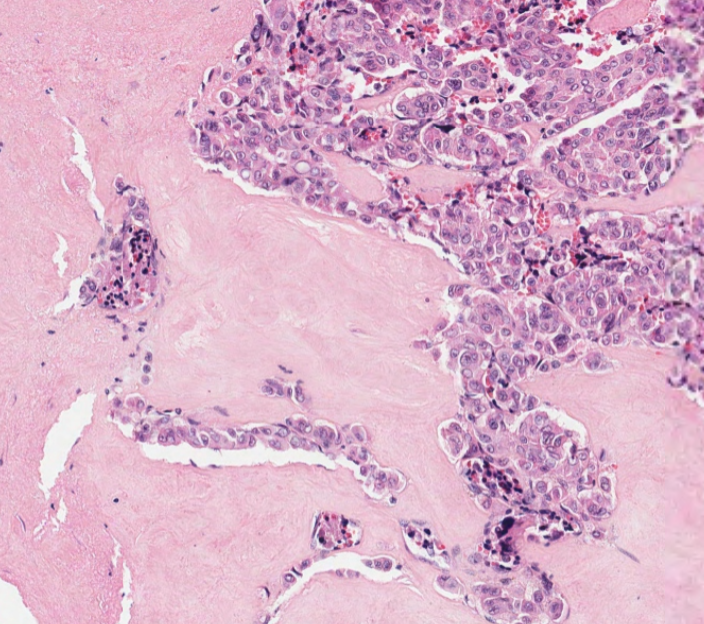

What neoplasm is causing this clavicular mass in a 65 year old man? View the whole slide on the Leeds Virtual Pathology Website here 🔬🔬🔬virtualpathology.leeds.ac.uk/slides/library… #softtissuepath #pathX #caseoftheweek